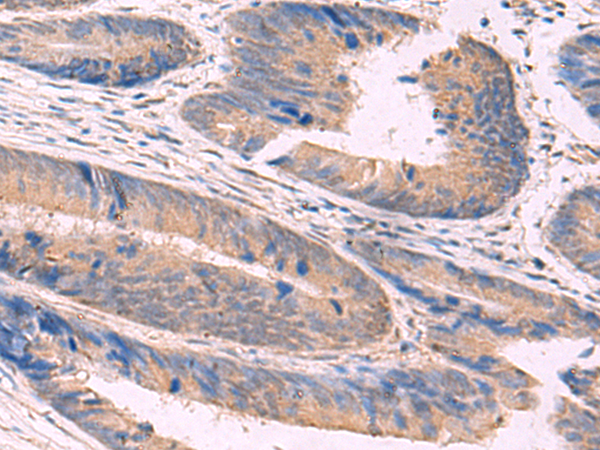

IHC (Immunohiostchemistry)

(The image is immunohistochemistry of paraffin-embedded Human colorectal cancer tissue using 47689(NIPSNAP1 Antibody) at dilution 1/50.(Original magnification: 200))